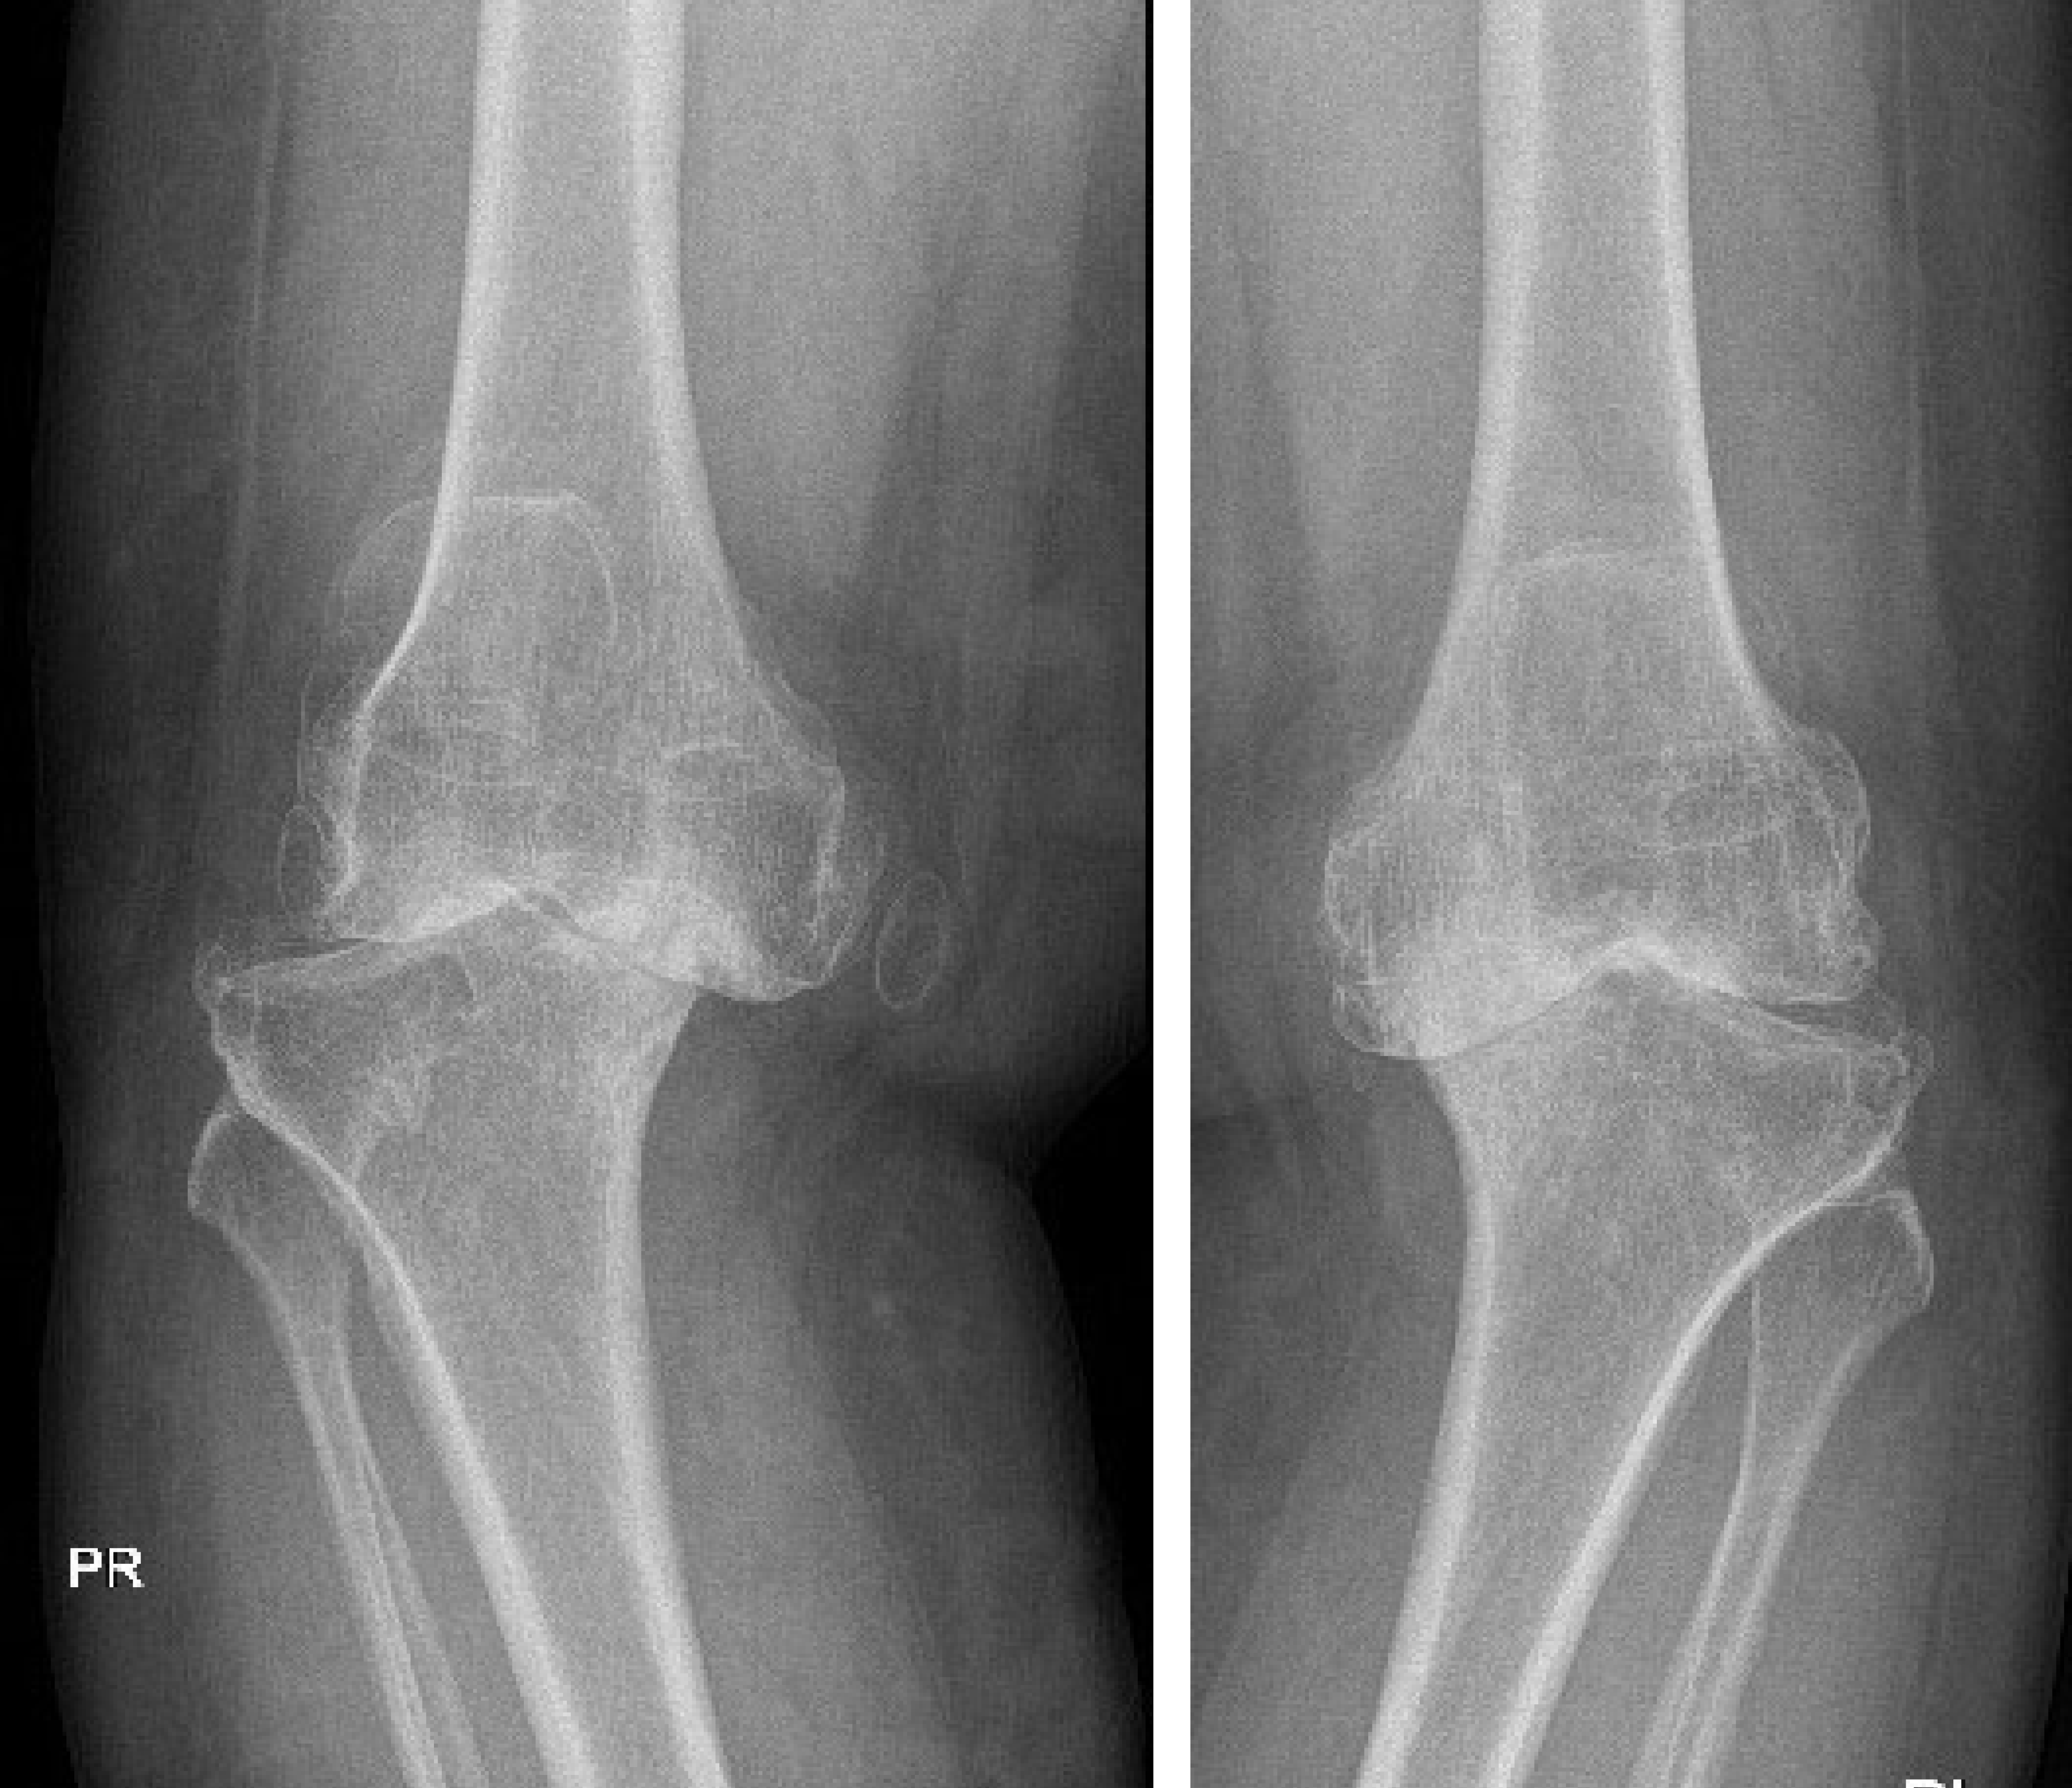

X-rays: To detect fractures or dislocations

Dislocations: Bones forced out of their normal position

Deformity or misalignment of fingers or wrist